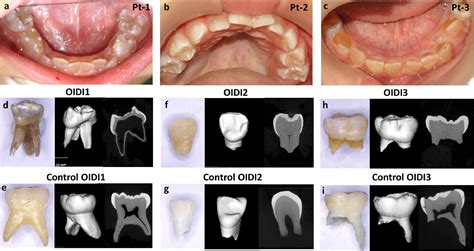

• Discoloration: Teeth often appear translucent, opalescent, or exhibit a blue-gray to yellow-brown hue.

• Radiographic Features: X-rays typically reveal bulbous crowns, a constricted cervical area, and abnormally thin roots. In some cases, pulp chambers may appear small or completely obliterated by secondary dentin formation.